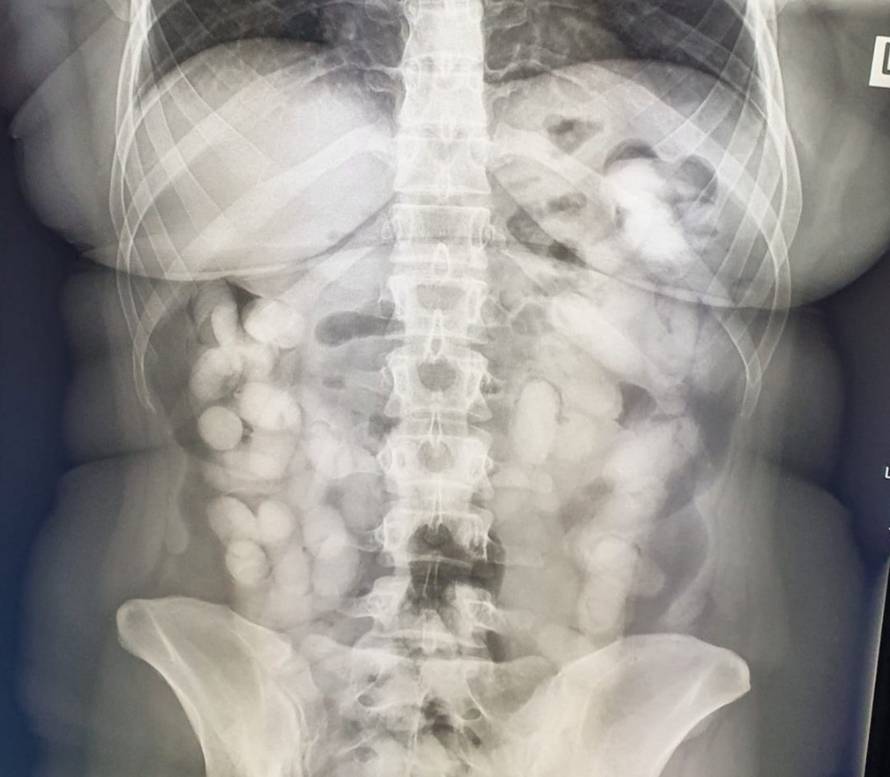

Ekskluzivne fotografije: Ovo je Brazilka koja je progutala kilu koke, doveli je u Veliku Goricu

Brazilka je u Zagreb stigla iz Sao Paula preko Lisabona što je odmah bilo sumnjivo carinicima jer je Portugal u Europskoj uniji, a carinski nadzor se ne provodi na putnicima koji dolaze iz zajedničke carinske unije